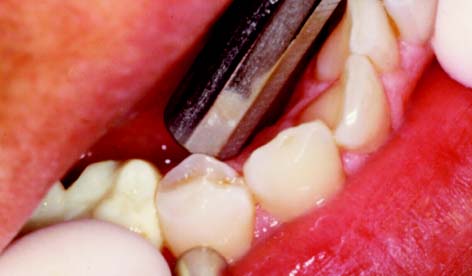

Fixed prosthodontic treatment involves the replacement and restoration of teeth by artificial substitutes that are not readily removable from the mouth. Its focus is to restore function, esthetics, and comfort. Fixed prosthodontics can offer exceptional satisfaction for both patient and dentist. It can transform an unhealthy, unattractive dentition with poor function into a comfortable, healthy occlusion capable of years of further service and greatly enhance esthetics (Fig. 1-1A and B). Treatment can range from the fairly straightforward restoration of a single tooth with a cast crown (Fig. 1-1C) or replacement of one or more missing teeth with a fixed dental prosthesis (Fig. 1-1D) or implant-supported restoration to a highly complex restoration involving all the teeth in an entire arch or the entire dentition.

Fig. 1-1 A severely damaged maxillary dentition (A) restored with metal-ceramic fixed prostheses (B). C, Complete cast crown restores mandibular molar. D, Three-unit fixed dental prosthesis replacing missing mandibular premolar.

(C, Courtesy of Dr. X Lepe. D, Courtesy of Dr. J. Nelson.)